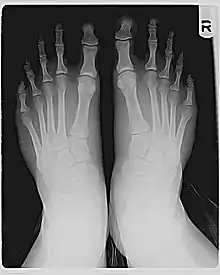

![]() السطح الظهري لقدم يمني بإصبع قدم مورتون (الصورة اليسري) وبدون (الصورة اليمني). تسيلط الضوء على الخط المتقطع

موقع المفصل. السطح الظهري لقدم يمني بإصبع قدم مورتون (الصورة اليسري) وبدون (الصورة اليمني). تسيلط الضوء على الخط المتقطع

موقع المفصل. | |

تختلف عظام المشط خلف أصابع القدم في الطول النسبي. بالنسبة لمعظم القدم، يمكن تتبع منحنى ناعم عبر المفاصل عند قواعد أصابع القدم. لكن في قدم مورتون، يجب أن ينحني الخط بشكل أكثر حدة لاختراق قاعدة إصبع القدم الكبير، كما هو موضح في الرسم البياني. وذلك لأن المشط الأول، وراء إصبع القدم الكبير، قصير مقارنة بالمشط الثاني الذي يجاوره. المشط الثاني الأطول يضع المفصل عند قاعدة إصبع القدم الثاني (المشط السلامي الثاني، أو MTP، المفصل) أكثر إلي الأمام.

إذا كان إصبع القدم الكبير والأصبع الثاني لهما نفس الطول (كما تم قياسه من مفصل MPT إلى الطرف، بما في ذلك الكتائب فقط)، فسوف يبرز إصبع القدم الثاني أبعد إلي الأمام من الإصبع الكبير، كما هو موضح في الصورة. إذا كان إصبع القدم الثاني أقصر من إصبع القدم الكبير، فقد يظل إصبع القدم الكبير الأكثر بروزة إلى أبعد مسافة، أو قد يكون هناك اختلاف بسيط، كما هو ظاهر في الأشعة السينية.